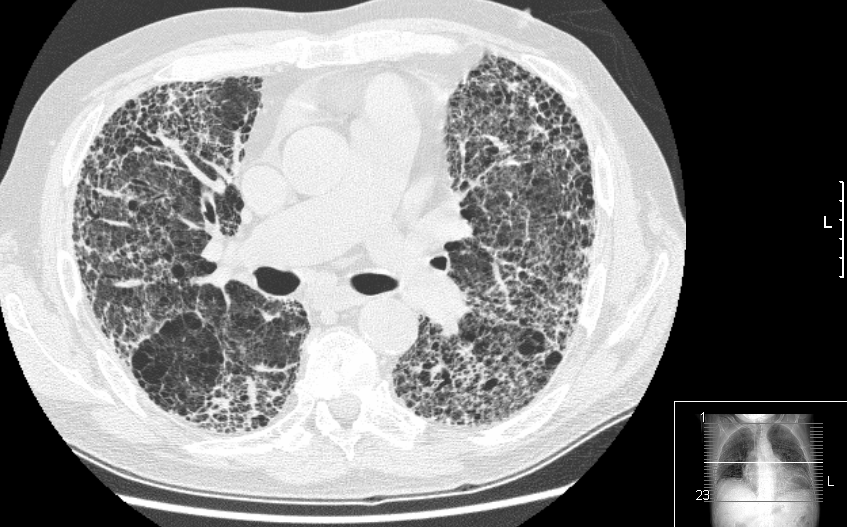

weekly clinical round for undergraduate from 8 to 11 AM during which interpretation of CHEST X rays was done for all cases of cardiothoracic surgery, gived by 2 staf member for 3 months